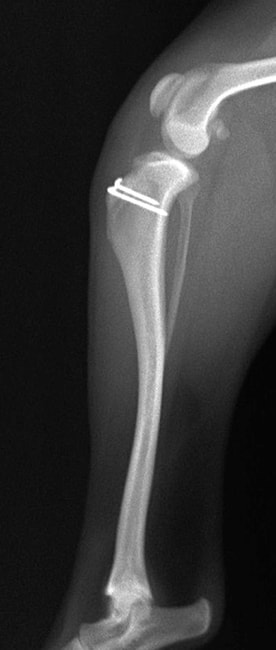

■ 症例22 ポメラニアン 1歳5か月 去勢雄

左後肢の挙上を主訴に来院した。整形学的検査、レントゲン検査より左右の膝蓋骨脱臼(左GradeⅡ〜Ⅲ、右Grade Ⅱ)を認めた。また、脛骨の前方引き出し試験の際に、引き出し兆候は認められないものの、疼痛が認められたため、前十字靭帯の損傷が疑われた。術中における、目視および関節内の操作によって、前十字靭帯の損傷や過伸展といった異常が認められなかったため、膝蓋骨脱臼の整復のみ実施した。手術手技は縫工筋及び内側広筋の解放、脛骨粗面の外側転位、滑車ブロック形造溝術、内外側関節包の縫縮を実施した。本症例は跛行もなく経過良好である。しかし、頸骨高平部の角度(TPA)が 右26.2°、左24.9°であり、解剖学的に前十字靭帯損傷のリスクが高いことから今後の経過に注意が必要である。